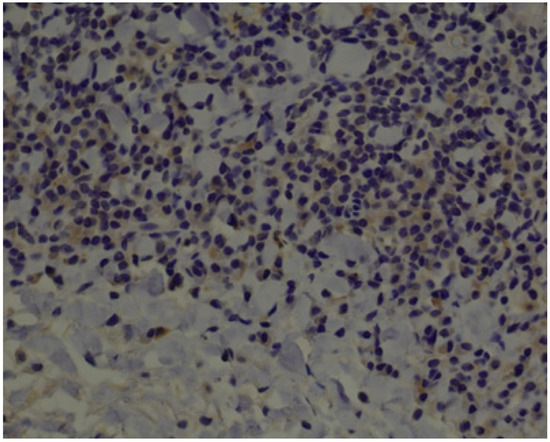

3.1. Histopathology and Immunohistochemistry

2.2. Histopathology and Immunohistochemistry